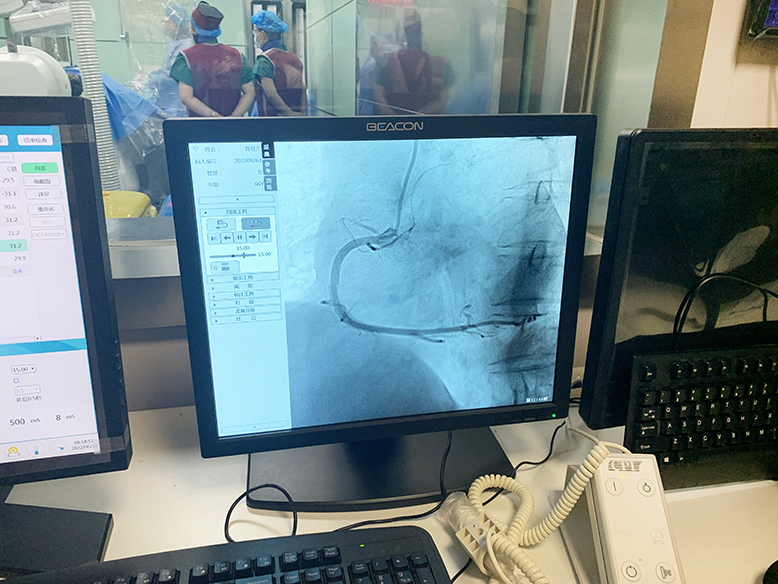

2022年6月16日,濱海新仁慈醫(yī)院在鄭州大學(xué)介入治療研究所的技術(shù)支持下,成功實(shí)施了兩例冠狀動(dòng)脈造影術(shù)(DSA),標(biāo)志著該院在心血管疾病的治療上邁上了新臺(tái)階。

經(jīng)術(shù)前充分準(zhǔn)備,上午8時(shí)手術(shù)順利開始。介入導(dǎo)管室內(nèi),兩位醫(yī)師緊張有序地操作,術(shù)中患者情況穩(wěn)定。上午9時(shí)許,在鄭州大學(xué)第二附屬醫(yī)院專家和濱海新仁慈醫(yī)院介入導(dǎo)管室團(tuán)隊(duì)的不懈努力下,手術(shù)順利完成。術(shù)后,患者無任何不良癥狀,安返病房。

據(jù)濱海新仁慈醫(yī)院介入導(dǎo)管室主任辛達(dá)路介紹,冠狀動(dòng)脈造影術(shù)是診斷冠心病的“金標(biāo)準(zhǔn)”。通過冠狀動(dòng)脈造影,可以了解冠狀動(dòng)脈血管分布,發(fā)現(xiàn)冠狀動(dòng)脈是否有狹窄以及血管狹窄程度。根據(jù)冠狀動(dòng)脈造影結(jié)果,決定是否對(duì)狹窄血管進(jìn)行支架置入術(shù)或者冠狀動(dòng)脈搭橋手術(shù)治療。